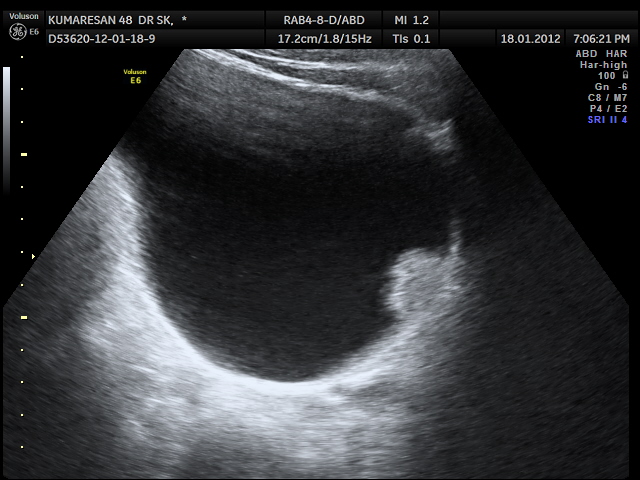

the last case was vesical calculi ; this one was a urinary bladder carcinoma .

47 year old man presented with complaints of painless hematuria ; he had a similar self limiting episode 3 months ago , which he ignored.His ultrasound pictures are given below